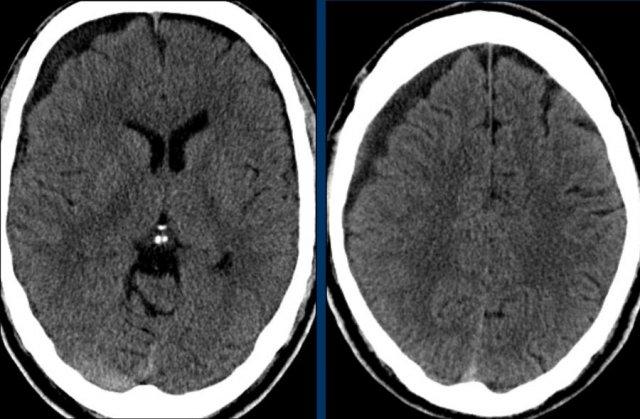

Tụ máu dưới màng cứng có thể lan dọc theo liềm não và lều tiểu não như trong trường hợp này.

Xuất huyết dưới nhện

Các hình ảnh cho thấy máu tăng tỷ trọng trong khoang dưới nhện của rãnh Sylvius (mũi tên vàng).

Lưu ý xuất huyết dưới da đầu vùng chẩm phải (mũi tên xanh).

Đây là dạng tổn thương chấn thương kiểu coup-contrecoup.

Đây là một trường hợp chấn thương kiểu coup-contrecoup khác với các xuất huyết dập não và tụ máu dưới màng cứng ở thùy trán trái gần nền sọ (mũi tên đỏ).

Có xuất huyết dưới nhện bên phải kèm gãy xương đỉnh (mũi tên vàng).